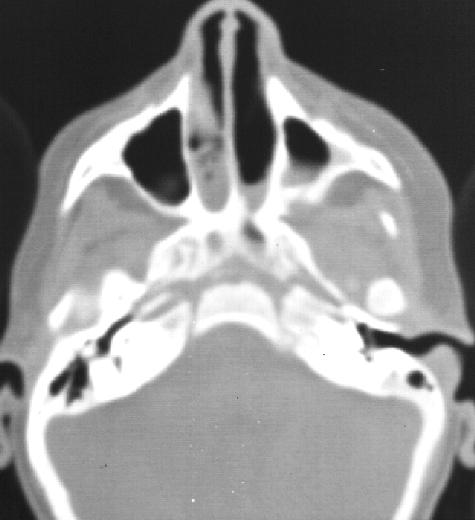

The current investigation of choice is CT and gives information whether the obstruction is membranous or bony and the actual structures involved and its thickness. It demonstrates thickening of the vomer, bowing of lateral wall of the nasal cavity and fusion of bony elements in choanal region. Congenital unilateral atresia is always associated with deviation of nasal septum and thickening of the vomer bone.

Axial CT image showing bilateral choanal atresia